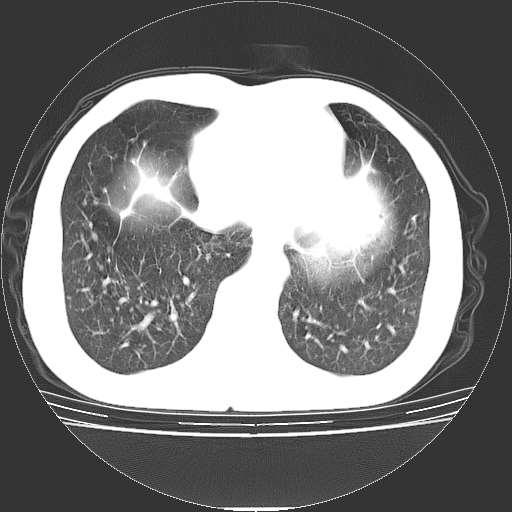

以下是引用yangyudong333在2008-4-29 5:38:00的发言:[br]比较典型的矽肺结节.支持[br]诊断依据:[br] 1.x线表现:[br] ①典型矽肺为多发直径 1~3mm 小结节,即矽结节,由胶原纤维和硅尘构成,可融合成团块,好发于上肺。[br] ②团块周围常有肺大泡。[br] ③胸内淋巴结增大、钙化。如肺门淋巴结呈蛋壳样钙化有助于与其他尘肺区别。[br] ④胸膜常广泛粘连、增厚。[br] 2.ct表现[br] ①两肺散在大小较为一致的小结节影,其密度较高,边界清楚。[br] ②小结节可融合为较大团块影,直径约 1cm ,甚至可达 10cm以上,易发生在上叶。[br] ③小结节周围常并有小叶中心气肿或弥漫性肺气肿。

以下是引用liuyue在2008-4-28 22:30:00的发言:[br]比较典型的矽肺结节.[br]请结合临床及化验除外矽肺合并肺结核之可能.